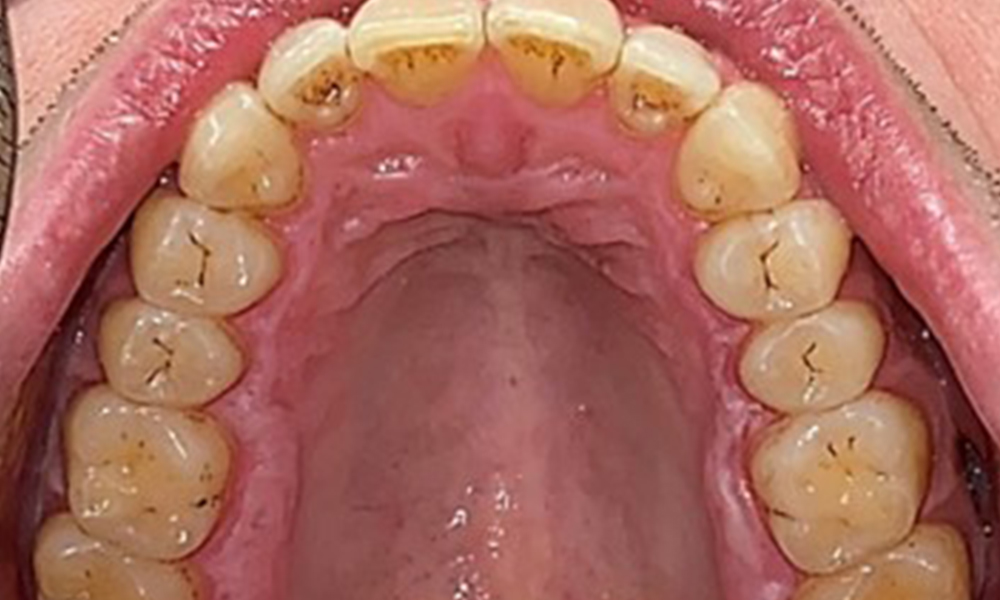

Extraoral sind keine pathologischen Befunde festzustellen, intraoral zeigen sich bei der Frontalansicht im Bereich der keratinisierten Gingiva und am Übergang zur beweglichen Schleimhaut bräunlicheVerfärbungen (Abb. 2), welche auf den Nikotingenuss zurückzuführen sind. Am Gaumenbereich zeigen sich insbesondere im Bereich Oberkiefermolaren palatinal weißliche Schleimhautveränderungen, die ein Hinweis auf einen erhöhten Verhornungsgrad sind und ebenso auf den Nikotingenuss zurückzuführen sind. Die Zunge ist mit einem weiß-bräunlichen abwischbaren Belag versehen.

Dentaler Befund

Dental zeigt sich ein vollbezahntes Gebiss mit 28 Zähnen. Auffällig sind Erosionen und Attritionen

(Abb. 4, Abb. 5). Der Patient trägt seit vielen Jahren nachts eine Schiene mit adjustiertem Aufbiss aufgrund Bruxismus. Die Erosionen sind auf den langjährigen Konsum isotonischer Getränke zurückzuführen. Parodontaler Knochenverlust und aktive kariöse Läsionen sind nicht vorhanden.